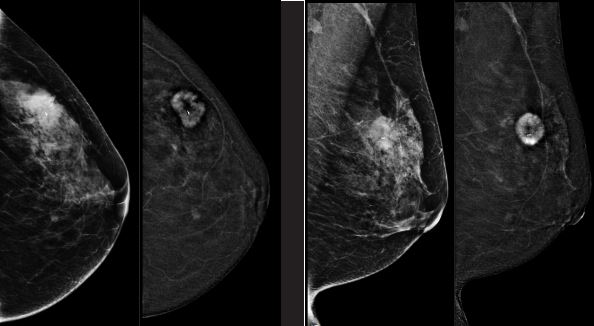

Wiadomości POWIAT Przychodnia LUX MED wznawia wykonywanie bezpłatnych badań mammograficznych, finansowanych przez NFZ, w ramach Programu Profilaktyki Raka Piersi.' w mobilnych pracowniach mammograficznych.

W badaniu mogą wziąć udział Panie w wieku 50-69 lat, które są ubezpieczone, nie są leczone z powodu raka piersi a także: nie miały wykonanej mammografii w ramach Programu w ciągu ostatnich 24 miesięcy lub są w grupie ryzyka i w roku poprzedzającym otrzymały pisemne wskazanie do wykonania ponownej mammografii po upływie 12 m-cy. Mammografia nie boli, polega na zrobieniu kilku zdjęć rentgenowskich piersi.

Na badanie należy zabrać ze sobą zdjęcia z poprzednich mammografii. Badania  nie wymagają skierowania, a pozwalają na wykrycie nowotworu na bardzo wczesnym etapie rozwoju choroby.  - Dlatego też, zachęcamy wszystkie panie, które z powodu pandemii nie mogły wykonać badań we wcześniej umówionym terminie o nie zwlekanie z rejestracją na mammografię – apelują orga

nizatorzy.